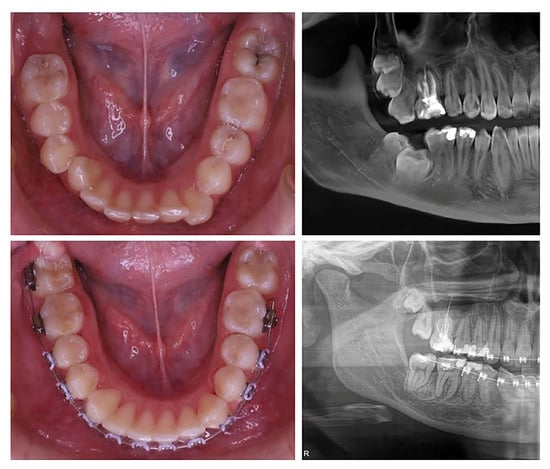

Figure 6. Clinical progression of the orthodontic traction of an impacted mandibular second molar: (a,b) Initial situation with vestibular and mesial inclination of tooth 47; (c,d) Vertical and lingual traction of the impacted molar using the PDaA system; (e,f) Final leveling of the mandibular dental arch following successful repositioning.

Figure 7. Intraoral photographs and radiographs of the impacted mandibular right second molar (tooth 47) before and after extrusion with a (PDaA) system.

The clinical sequence and outcomes associated with the management of impacted mandibular second molars (MM2) utilizing customized, metal-printed dentoalveolar anchorage systems (PDaA) are illustrated in Figure 6 and Figure 7. Following the extraction of the mandibular third molars and the surgical exposure of the impacted teeth, performed in accordance with the digital treatment plan, orthodontic buttons were bonded to the MM2. After a healing period of 3–4 days, the PDaA was cemented intraorally.

The position of the extension arm within the retromolar space and the predesigned anchorage points allowed for precise control over the vector and direction of the applied orthodontic force, with the possibility of modification during tooth movement. The arm followed the contour of the alveolar ridge and the course of the ascending ramus, enabling the use of planned hook points to direct vertical movements of the impacted second molar. Thus, control is achieved in the bucco-lingual, vertical, and disto-coronal directions simultaneously. The anchorage point on the PDaA system was adjustable during treatment according to the required direction of tooth movement. Activation of the elastic element was carried out every 3–4 weeks during routine orthodontic follow-ups. The applied force system generated a counterclockwise moment, enabling controlled movement. The roots of the MM2 moved mesially, consistent with their biological eruptive path and toward an area of greater bone volume. Side effects were minimized, and anchorage components were incorporated to offset undesirable forces. Once sufficient uprighting and vertical alignment of the MM2 were achieved, the extension arm or the entire PDaA system was removed. The subsequent treatment phase involved leveling of the dental arch and restoration of functional occlusion. In some clinical cases, brackets or tubes were added to the anchorage teeth on the PDaA, integrating it into the fixed orthodontic appliance.

The effectiveness of PDaA is best illustrated by a clinical case. The treatment stages presented in Figure 6 were on a 17-year-old female patient diagnosed with impaction of the mandibular right second molar (tooth 47), hyperdontia involving the maxillary right third molar (tooth 18), and rotations in both arches.

Tooth 47 had its crown positioned mesially and buccally, with the roots in contact with the lingual cortical plate of the mandible. The mandibular right third molar (tooth 48) completely blocked the eruptive potential and path of tooth 47, necessitating extraction of tooth 48. To address the supernumerary maxillary molar, extraction of the maxillary right second molar (tooth 17) was planned to create space for eruption of the third molar(s).

The patient was treated using a PDaA to upright the mandibular right second molar (47), combined with extraction of the maxillary right second molar (17) and comprehensive leveling of both arches while preserving Class I relationships. The PDaA phase lasted six months, resulting in complete uprighting and extrusion of tooth 47, shown on Figure 6. Forces were applied to achieve lingual uprighting, followed by distal crown tipping. The distally extended arm provided an extrusive vector to bring tooth 47 to the occlusal plane. Fixed appliances were subsequently bonded in both arches to complete leveling and alignment Figure 6 and Figure 7.